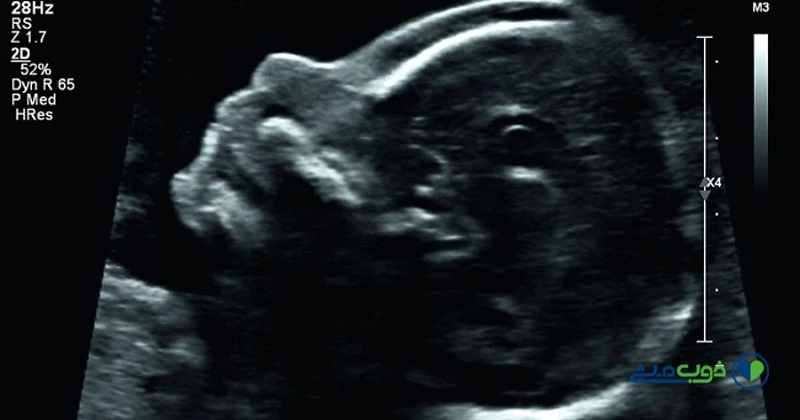

- سونوگرافی: در سونوگرافی تجمع مایع پشت گردن جنین (NT) اندازه گیری میشود.

- سونوگرافی NT: در سونوگرافی NT، عدد ان تی باید کمتر از 3 باشد. هرچقدر عدد از 3 بیشتر باشد احتمال خطر سندروم دان نیز افزایش مییابد.

تشخیص سندرم داون در جنین فقط به عهده پزشک معالج است زیرا مادر باردار خود هیچگونه علائمی ندارد و تنها با آزمایشات غربالگری میتوان نتیجه را با اطمینان مطرح کرد. در سونوگرافیها تیغه استخوان بینی جنین، ظاهر ساختاری ارگانهای مختلف مانند کلیه، قلب و اندامهای دست و پا مورد بررسی قرار میگیرد و در صورتی که مورد مشکوک دیده شود هشدار داده میشود. گاه نتایج حاصل شده مثبت کاذب است و کودکی سالم به دنیا میآید و گاه مورد مشکوکی مشاهده نمیشود و با به دنیا آمدن نوزاد تشخیص سندرم داون میسر است. بالا بودن سن مادر (35 سال به بالا)، ازدواج فامیلی، مبتلا بودن یکی یا هر دو والدین به سندرم داون و وجود بیماریهای ژنتیکی احتمال وجود سندرم داون را در جنین افزایش میدهند.